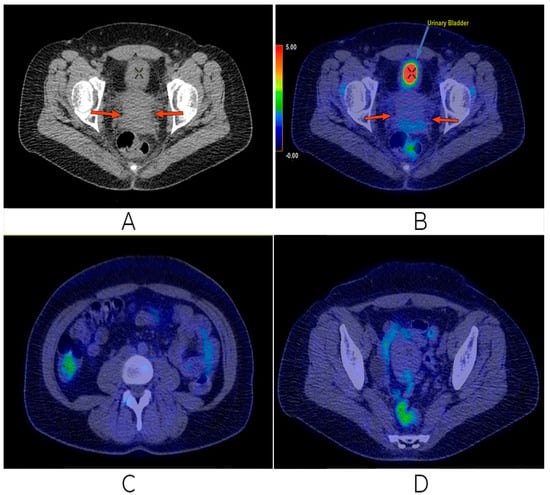

2.2. Imaging, Treatment Strategies, and Response